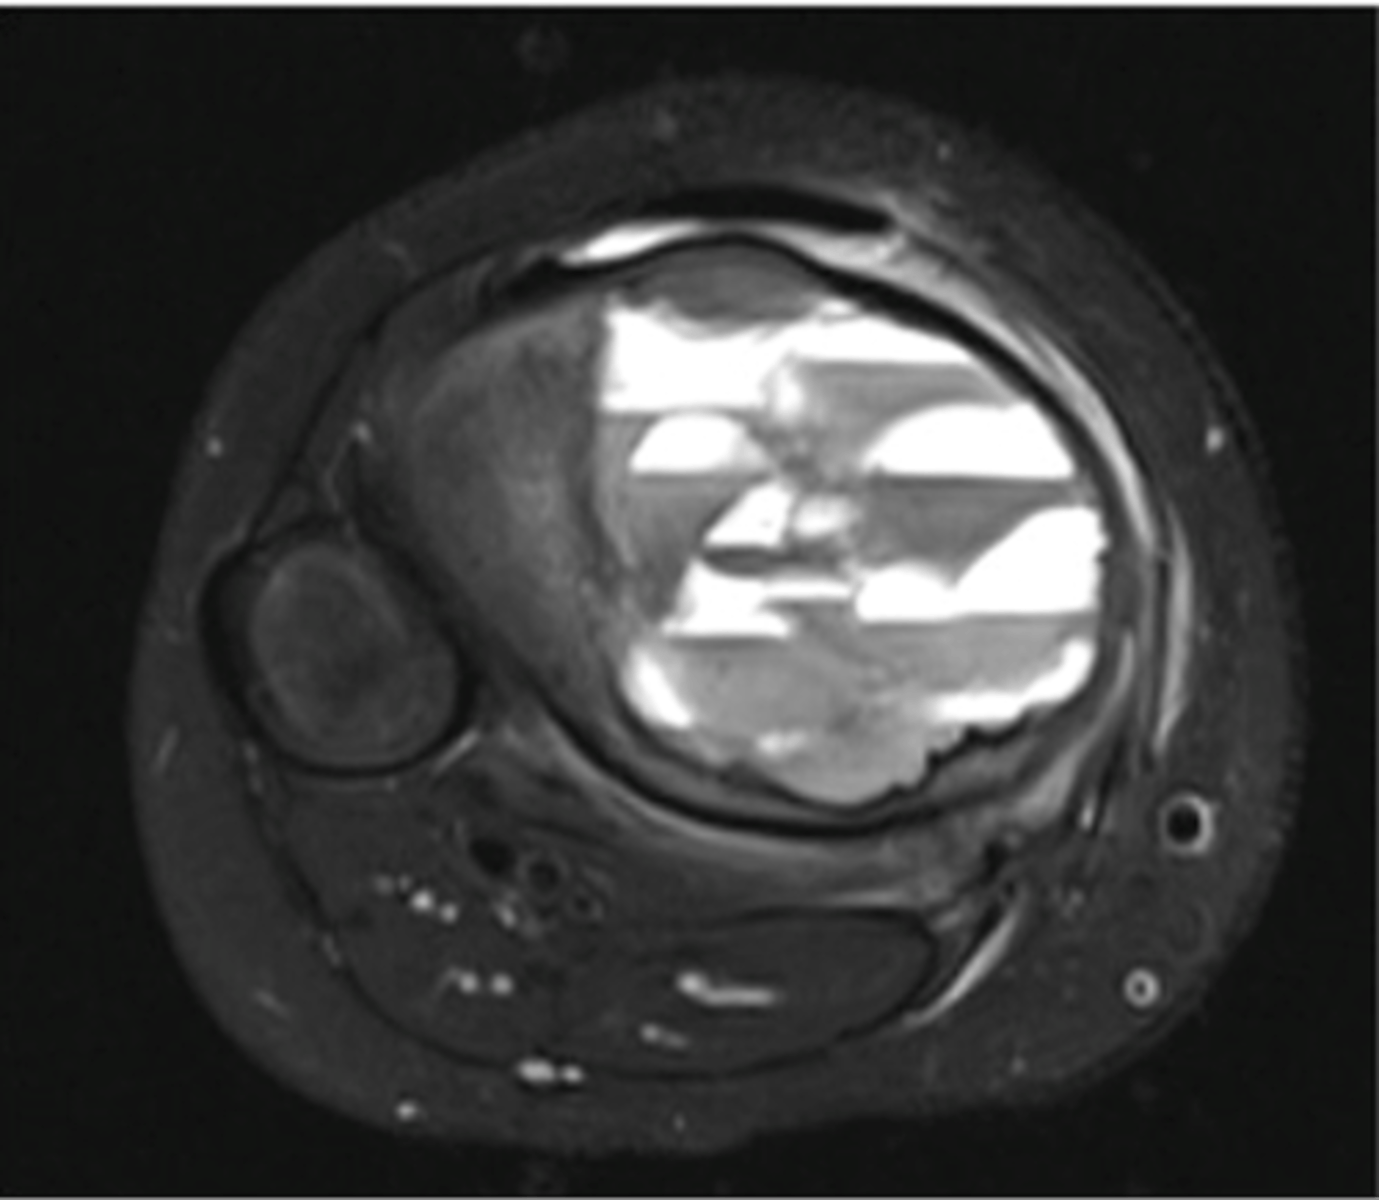

Fluid-Fluid Levels

- Most compatible with aneurysmal bone cyst

- Also seen in giant cell tumors, simple bone cysts, and telangiectatic osteosarcoma